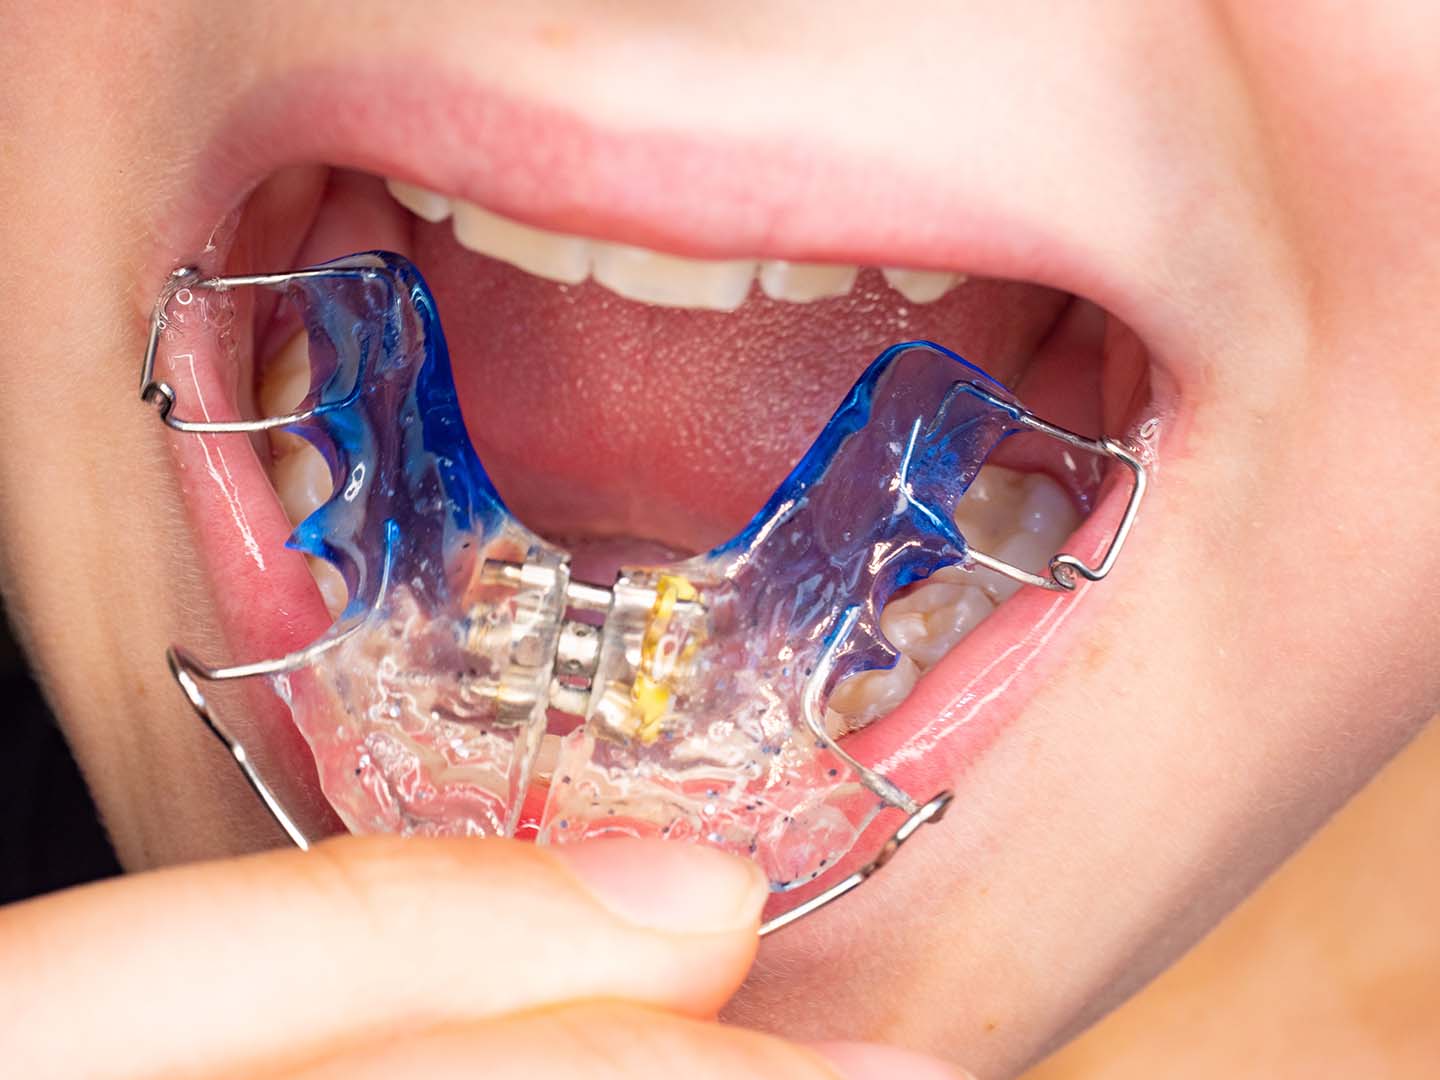

Mediante una exploración radiográfica, este determinará si es el momento adecuado para la colocación de un aparato expansor que recupere la forma normal del paladar. Este tipo de tratamiento se debe realizar en la edad infantil ya que el resultado de la expansión es estable en el tiempo, y permite la normalización del desarrollo tanto de los huesos como de los dientes.

Por lo general, en Raga Ortodoncia optamos por un aparato fijo para que actúe a nivel de hueso y no solo de dientes, y que el pronóstico sea favorable. Este tipo de aparato permite desarrollar una fuerza necesaria y se suele llevar puesto en boca entre 9 meses y 1 año, según el caso del paciente.